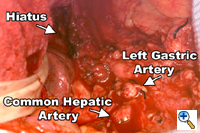

Figure 5. This view of the upper abdomen reveals the extent of the retroperitoneal lymphadenectomy superior to the upper border of the pancreas. Figure 5. This view of the upper abdomen reveals the extent of the retroperitoneal lymphadenectomy superior to the upper border of the pancreas. |

The abdomen is entered through a mid-line incision. The omentum is separated from the colon in the avascular plane and the lesser sac is entered. Following division of the short gastric vessels, the retroperitoneum is incised along the superior border of the pancreas. The retroperitoneal lymphatic and areolar tissues are swept superiorly towards the esophageal hiatus and medially along the splenic artery to the celiac trifurcation. The left gastric artery is divided flush with its celiac origin and the nodes along the common hepatic artery are dissected towards the specimen. This retroperitoneal dissection is bounded by the dissected esophageal hiatus superiorly, the hilum of the spleen laterally and the common hepatic artery and inferior vena cava medially (Figure 5). Finally, the lesser curvature and left gastric nodes are included with the specimen as the gastric tube is prepared. The omentum is resected as a separate specimen at least one inch outside the gastroepiploic arcade.